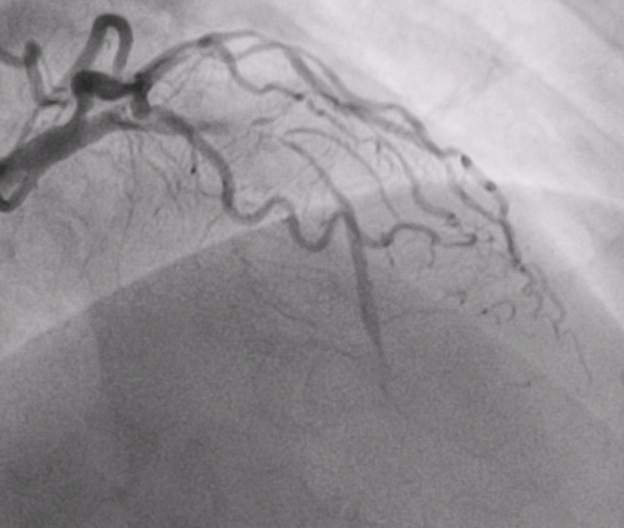

术前患者冠脉造影

安徽人陈先生远在新疆工作,因快走后出现胸闷症状且越来越严重于当地医院就诊,冠脉造影显示冠状动脉多支多处严重弥漫性狭窄,病情十分凶险,医生建议他立即开胸做搭桥手术,但是由于血管病变太严重,手术风险极高,很有可能下不来手术台。陈先生和家人一筹莫展之际,有人向他们推荐了湖南省人民医院心血管内科三病区潘宏伟主任团队,了解到潘宏伟主任团队擅长冠脉介入诊疗,尤其是在疑难复杂的病变方面,临床经验非常丰富,于是陈先生与家人决定连夜打“飞的”往湖南求诊。

陈先生入院后,潘宏伟主任团队对其病情进行了全面评估,制定了详细周密的诊疗计划,于1月27日行介入支架治疗开通了几乎完全闭塞的前降支血管,术后效果“立竿见影”,陈先生的胸闷症状立马消失了。由于陈先生冠脉多支多处弥漫性狭窄严重,要想修复所有的血管还需要在多处植入药物球囊,手术难度较大,加上年后就可以享用集采的价格,于是建议他调理两月再来。近日,陈先生从遥远的新疆再次打“飞的”来长沙行第二次手术,4月12日潘宏伟主任团队采用了支架+药物球囊的组合方式,完美的修复了非常复杂的冠状动脉,术后经过精心护理,陈先生于4月15日康复出院。